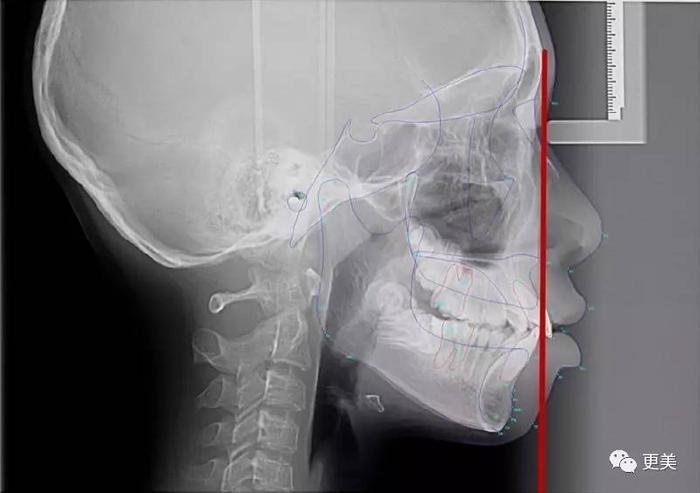

而嘴凸也分牙性和骨性的,要确定自己属于哪种情况必须要去拍片哦

通常会拍到这三种情况,额头到牙齿画线,上颌没有超线的,就是牙性问题;如果超出了,可能就是骨性问题了

所长找了张X光片来做例子,大家可能会看得更清楚,这种就是牙性问题

经过矫正以后,凸出的牙齿回缩到正确的位置,龅牙问题就可以解决了

但如果是骨性问题,单靠矫正牙齿,是无法完全解决嘴凸的,例如下面这个片子上的